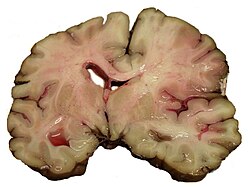

Hemoragijski moždani udar

Intrakranijska hemoragija (krvarenje) je nakupljanje krvi bilo gdje unutar lubanjskog svoda. Postoji razlika između intra-aksijalnog krvarenja (krv unutar mozga) i eksta-aksijalnog krvarenja (krv unutar lubanje, ali izvan mozga). Intraaksijalno krvarenje unastaje zbog intraparenhimalnog krvarenja (krv u moždanom tkivu) ili intraventrikularnog krvarenja (krv u ventrikularnom sustavu). Glavne vrste ekstraaksijalnog krvarenja su epiduralni hematom (krv između dure mater i lubanje), subduralni hematom (u subduralnom prostoru) i subarahnoidalno krvarenje (između arahnoideja i pije mater). Većina sindroma hemoragijskih moždanih udara ima specifične simptome (npr. glavobolja, prethodna ozljeda glave).